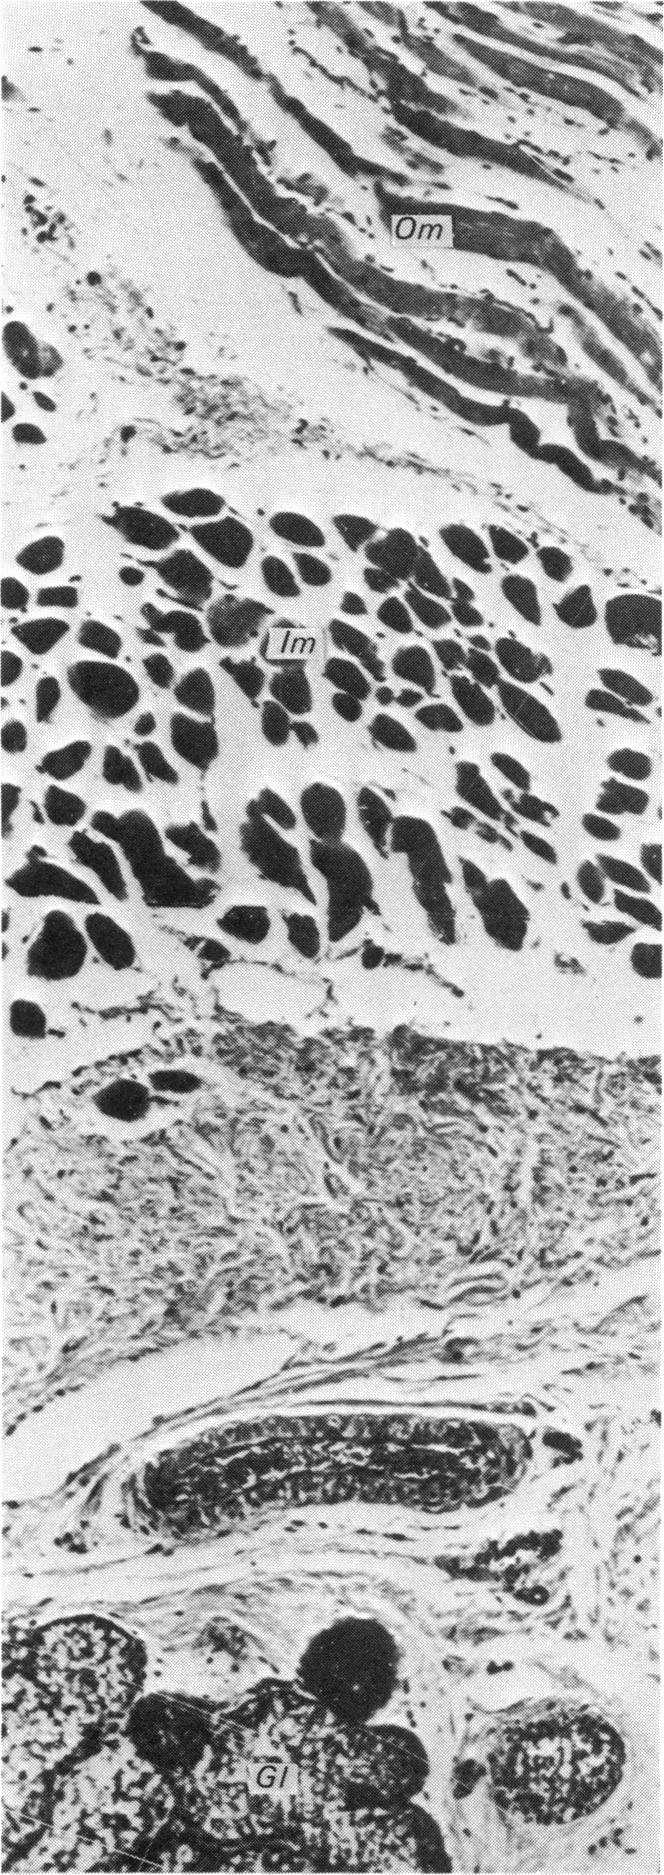

The histological structure of the oesophagus of the camel in different parts of its course was investigated with tissues from seven camels, and with haematoxylin and eosin and Masson's trichrome stain. Gross dissections confirmed the orientation of the muscle fibres in the tunica muscularis. The epithelium showed heavy cornification. Many submucosal mucous glands were found throughout the length and all round the wall of the oesophagus. This was contrary to what has been reported generally for ruminants. The lamina muscularis mucosae was in the form of small scattered strands of smooth muscle (more readily identifiable with trichrome stain) and only in the caudal oesophagus. It did not form a continuous layer here. The tunica muscularis was of striated type throughout which agreed with what has been found in the other ruminants. Its fibres, however, were differently oriented. The outer tunica was mainly circular (especially in the mid-thoracic part) and the inner one was mainly longitudinal in direction. Mixed orientation of the muscle fibres in parts of the same section was also noticed. These findings have not been reported previously in the camel.